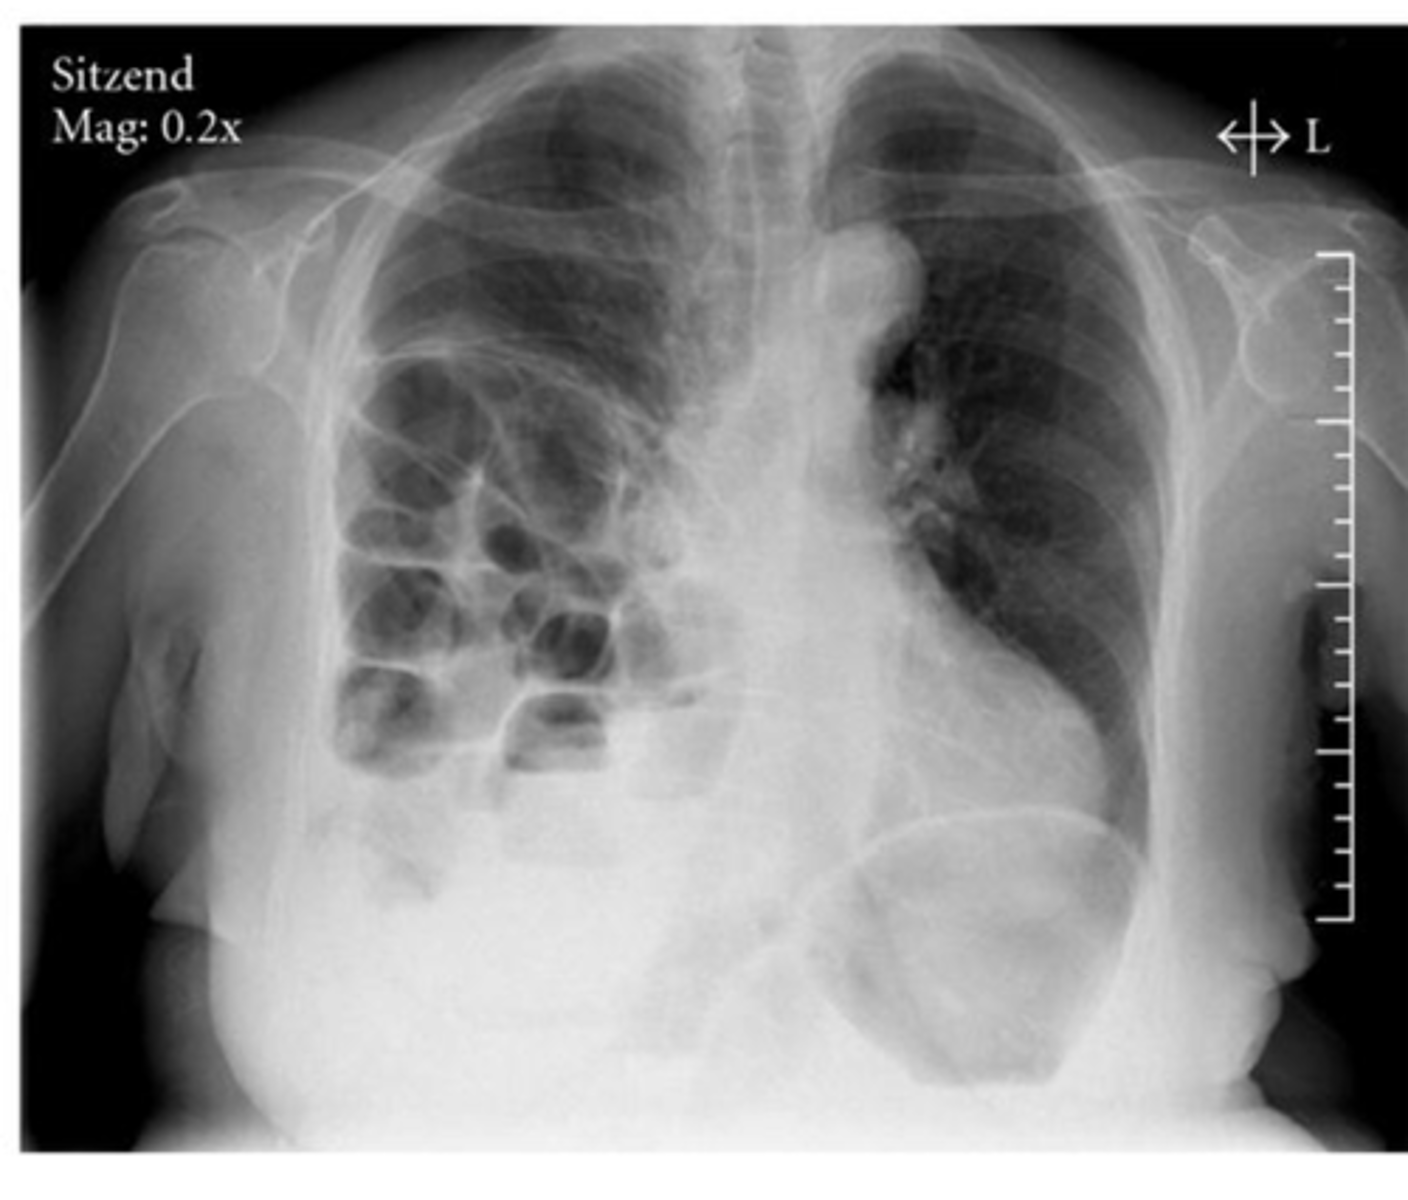

Flattened diaphragms, ant mediastinal space increased --> COPD/emphysema

Dx and ID radiological findings

<p>Dx and ID radiological findings</p>

-Flattening of hemidiaphragms with blunting of costophrenic angles.

-Increased AP diameter of chest on lateral view (barrel chest)

-Presence of bullae or large air cavities

What x-ray findings are found in advanced stages of COPD/emphysema?